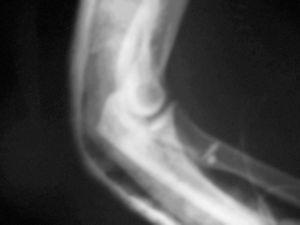

Se realiza una incisión curvilÃnea en la cara anterior del codo. Se continúa con una disección cuidadosa por planos, llegando a la aponeurosis profunda que se corta longitudinalmente para localizar el tendón distal del bÃceps que habitualmente se retrae unos 5 o 6 centÃmetros por encima del codo (fig. 3). Mientras se hace esta disección hay que proteger el nervio cutáneo externo del antebrazo. Se localiza la tuberosidad bicipital del radio para la reinserción del tendón. Las reinserciones y suturas se realizaron en diez casos (76,9%) con reanclaje mediante arpones (fig. 4), en dos casos con túneles óseos (15,4%), y en uno mediante un anclaje con técnica endobutton (7,7%). Los arpones utilizados fueron de distintas casas comerciales, pero siempre roscados y de 3,5 milÃmetros de grosor (fig. 5). En 5 roturas (50%) se utilizó un único arpón (fig. 4), 4 lesiones (40%) se reanclaron con 2 arpones y 1 (10%) con 3 (fig. 5).

Figura 5. Proyección radiográfica lateral que muestra la situación de los arpones. Control postoperatorio.